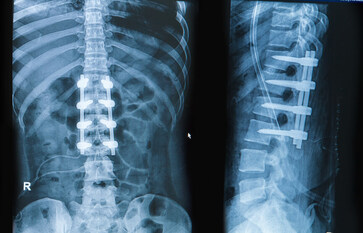

Chirurgien expérimenté

Le cabinet médical est spécialisé dans la chirurgie du rachis depuis 1985. Le Docteur Chiffolot réalise plus de 2500 consultations du dos et plus 520 interventions par an du rachis entier (hernie discale, arthrodèse lombaire…).